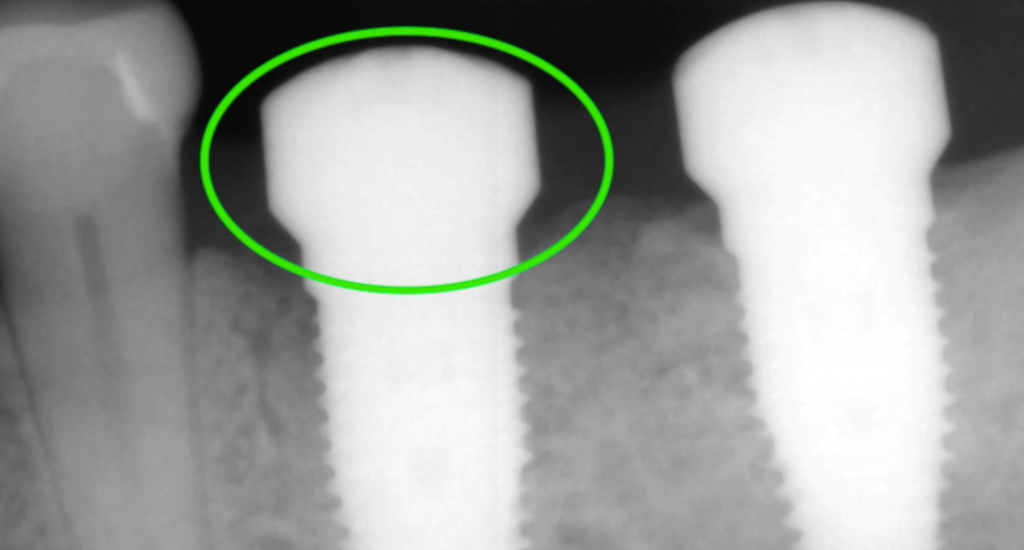

Non-Invasive Removal of Abutment and Dental Implant in the Aesthetic Zone

Removal of a dental implant with bone loss and poor position resulting in compromised aesthetics and appearance; Demonstration of how an implant can be removed with no incision or bone removal, even in circumstances where the implant has been in place for years and fully integrated.